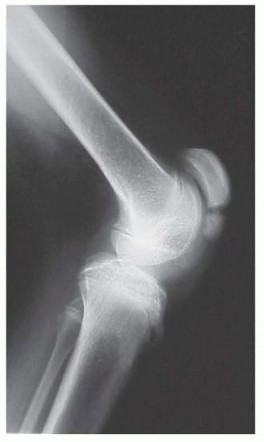

Standardized standing radiographs are mandatory. An anteroposterior (AP) pelvis film assesses for hip subluxation or dysplasia, which frequently co-occurs in spastic diplegia and may alter the surgical plan. Standing long-leg alignment films evaluate for coronal plane malalignment. Crucially, a standing lateral radiograph of the knee is scrutinized for patella alta (measured via the Insall-Salvati or Caton-Deschamps ratios) and fragmentation of the inferior pole of the patella. The presence of these radiographic findings confirms chronic patellofemoral overload and solidifies the indication for intervention to rescue the joint.